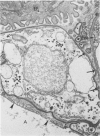

In order to characterize the alveolar response to Pneumocystis carinii pneumonia, light and electron miscropy were used to trace the development of experimental infections with P carinii in rats treated with cortisone acetate and a low-protein diet. The first changes were found by the eighth day of treatment and consisted of the selective attachment of Pneumocystis organisms, mostly trophozoites, to alveolar Type 1 pneumocytes; the host cells were undamaged, and no inflammatory response was seen. After approximately one month of treatment, the seemingly innocuous host-parasite interaction was succeeded by focal necrosis of the Type 1 pneumocytes adjacent to organisms; hyperplasia of nearby Type 2 pneumocytes also occurred, to replace the dead Type 1 pneumocytes. Even at this stage, inflammatory reaction was conspicuously absent except for occasional alveolar macrophages in the diseased alveoli; in addition, all cells of the alveolar-capillary membrane other than Type 1 pneumocytes appeared entirely normal. Not only does the present study clarify the nature of alveolar injury caused by Pneumocystis carinii, but it also provides an experimental animal model in which selective injury of the alveolar lining cells occurs.